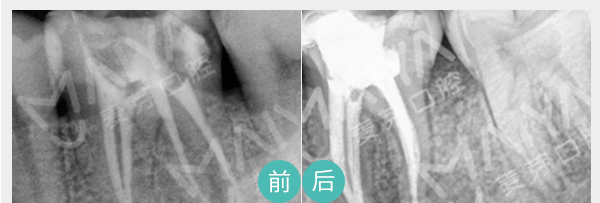

麦芽显微根管治疗